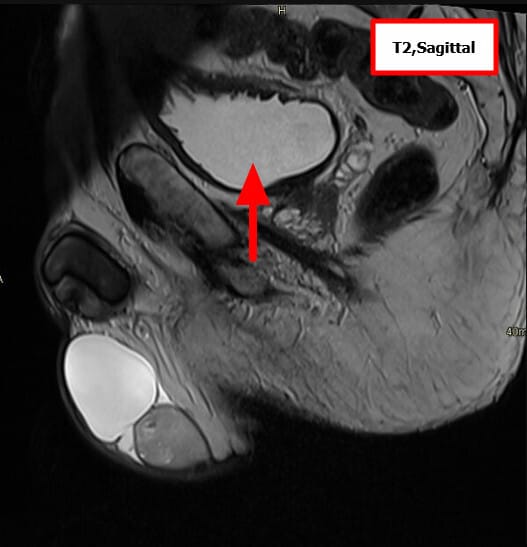

고환암 영상 소견

고환암 – Seminoma

– 가장 흔한 고환 생식세포 종양

– 방사선 민감성이 높아 예후가 좋은 편

– 주로 젊은 남성(30~40대)에서 발생

[정의]

– Seminoma는 고환에서 발생하는 대표적인 생식세포 종양(Germ cell tumor)입니다.

– 단일 세포 형태가 균일하고, 방사선 치료에 잘 반응하는 특징을 지니며, 비교적 예후가 좋은 악성 종양입니다.

[원인/위험요인]

– 가장 중요한 위험 요인은 잠복고환(cryptorchidism)입니다.

– 가족력(고환암 병력 있는 형제/부계).

– 고환 발달 이상(Klinefelter syndrome 등).

– 백인에서 상대적으로 높은 발생률.

[임상양상]

– 무통성 고환 종괴

– 진행 시 복부·골반 림프절 전이에 따른 허리 통증이나 복부 종괴.

– 드물게 여성형 유방(호르몬 분비 종양 시)이 동반될 수 있습니다.

[진단]

– 신체검사: 단단한 고환 종괴 촉지.

– 종양표지자: hCG 상승 가능, 그러나 AFP는 정상

– 영상검사: 고환 초음파에서 저에코성 종괴 확인.

– CT/MRI: 병기 설정 및 전이 평가.

– 확진: 고환 절제술(근치적 고환 절제술, radical orchiectomy)을 통한 조직학적 확인.